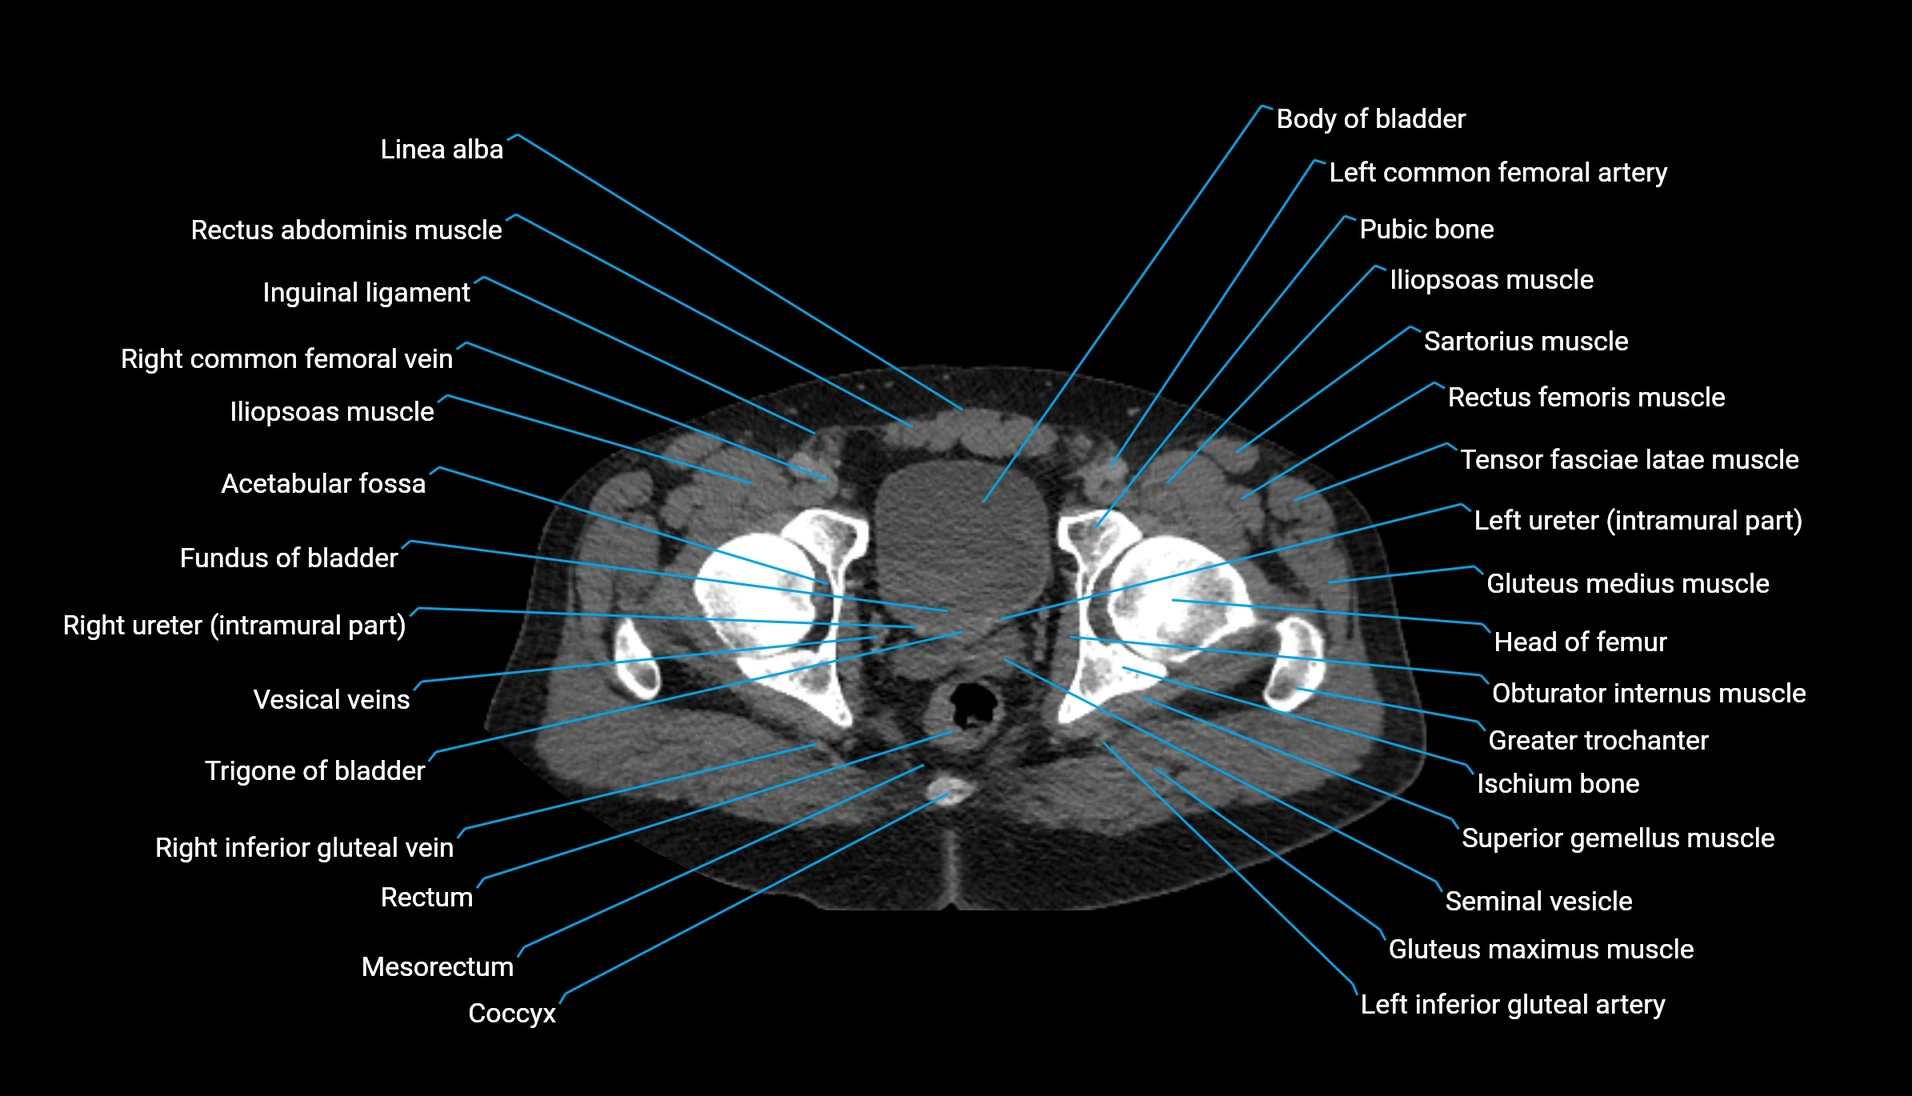

The acetabular margin, also called the acetabular rim, is the bony edge of the acetabulum, the cup-shaped cavity on the lateral aspect of the pelvis that articulates with the head of the femur to form the hip joint. The acetabular margin consists of the superior, anterior, and posterior borders of the acetabulum and is interrupted inferiorly by the acetabular notch.

The rim provides attachment for the acetabular labrum, a fibrocartilaginous structure that deepens the acetabulum, increasing hip joint stability. The transverse acetabular ligament bridges the acetabular notch, completing the bony ring. Superiorly, the margin bears the greatest load during standing and gait, making it the most common site of degenerative changes.

The acetabular margin is clinically significant in femoroacetabular impingement (FAI), acetabular fractures, hip dysplasia, and osteoarthritis. Its morphology (depth, coverage, and orientation) is a key factor in hip biomechanics and surgical planning, especially in arthroscopy and hip preservation surgery.

CT Appearance

Non-contrast CT:

-

Demonstrates cortical bone of acetabular rim in excellent detail

Detects fractures, dysplasia, retroversion, or bony overcoverage (pincer impingement)

3D reconstructions used in preoperative hip surgery planning

CT Post-Contrast (CT Arthrography):

Joint contrast outlines the acetabular labrum, cartilage, and margin

Demonstrates labral tears, cartilage defects, and subtle bony abnormalities

Alternative to MR arthrography in patients with MRI contraindications

CT VRT 3D image

CT image